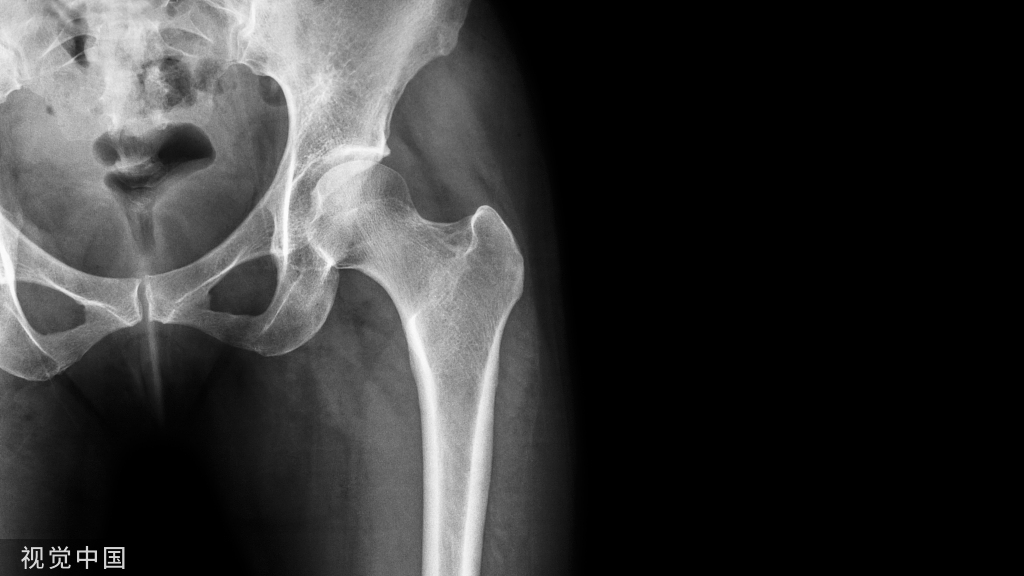

X线显示:全口牙槽骨广泛性混合吸收至根长的1/3~2/3(图4)。

图4  病例2患者曲面断层片